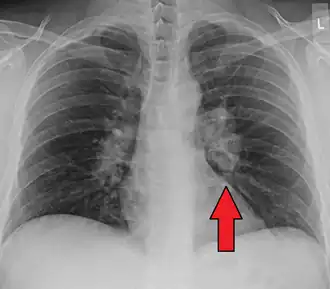

![]() | |

| Chest X-ray showing the typical nodularity of sarcoidosis, predominantly in the hila of the lungs. | |

Chest radiograph changes are divided into four stages:[104]

- bihilar lymphadenopathy

- bihilar lymphadenopathy and reticulonodular infiltrates

- bilateral pulmonary infiltrates

- fibrocystic sarcoidosis typically with upward hilar retraction, cystic and bullous changes

Although people with stage 1 radiographs tend to have the acute or subacute, reversible form of the disease, those with stages 2 and 3 often have the chronic, progressive disease; these patterns do not represent consecutive "stages" of sarcoidosis. Thus, except for epidemiologic purposes, this categorization is mostly of historic interest.[28]